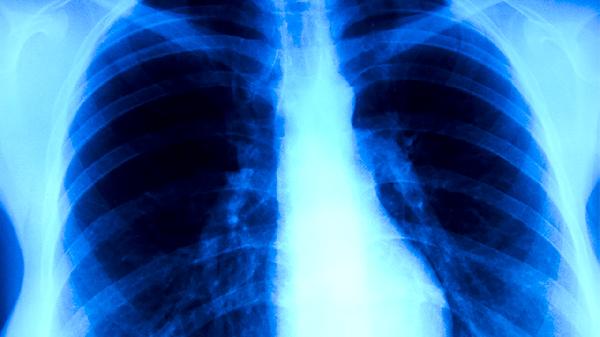

肺結(jié)核可通過接種卡介苗、保持通風(fēng)、佩戴口罩、增強(qiáng)免疫力、定期篩查等方式預(yù)防。肺結(jié)核是由結(jié)核分枝桿菌感染引起的慢性傳染病,主要通過飛沫傳播。

結(jié)核菌素試驗(yàn)或γ-干擾素釋放試驗(yàn)適合高風(fēng)險(xiǎn)人群篩查??人钥忍党^2周者需進(jìn)行痰涂片和胸部X線檢查。密切接觸者應(yīng)每半年復(fù)查一次,學(xué)生及醫(yī)務(wù)人員建議每年體檢。發(fā)現(xiàn)疑似癥狀應(yīng)立即到結(jié)核病定點(diǎn)醫(yī)療機(jī)構(gòu)就診。

日常生活中應(yīng)注意與咳嗽患者保持1米以上距離,不隨地吐痰,咳嗽時(shí)用肘部遮擋口鼻。保證每日攝入300克新鮮蔬菜和200克水果,適量食用大蒜、洋蔥等具有抗菌作用的食物。出現(xiàn)長(zhǎng)期低熱、盜汗、消瘦等結(jié)核中毒癥狀時(shí),須及時(shí)進(jìn)行結(jié)核菌檢測(cè)和影像學(xué)檢查。確診患者應(yīng)嚴(yán)格完成6-8個(gè)月的規(guī)范治療,避免產(chǎn)生耐藥性。